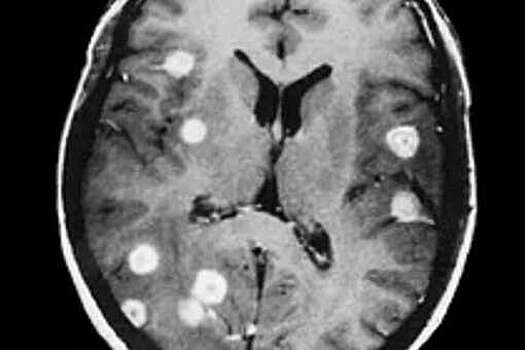

Исследователи из Медицинского Университета в Вене показали, что метастазы в мозге у пациентов с раком молочной железы частично или даже полностью регрессируют под действием комбинации двух активных веществ. Результаты работы опубликованы в журнале Nature. В исследовании приняли участие 14 женщин и один мужчина с HER2-положительным раком молочной железы. Все пациенты имели метастазы в головном мозге и находились на лечении в отделении онкологии Медуниверситета Вены и Университетской больнице Вены. Команда врачей изучила влияние экспериментального препарата, трастзумаба дерукстекана (T-Dxd), на их метастазы. T-Dxd уменьшил метастазы у 73,3% пациентов, а у двух (13,3%) — привел к их полному исчезновению. Исследователи также обнаружили, что препарат хорошо переносился: в период лечения не было ухудшения функции мозга или качества жизни участников. T-Dxd уже одобрен в ЕС и некоторых странах за пределами Европы, поэтому ученые считают, что уже сейчас его можно использовать в клинической практике для лечения пациентов с метастазами. 15% больных раком молочной железы имеют HER2-положительный рак молочной железы. Метастазы в головном мозге появляются у 50% пациентов с HER2-положительным. До сих пор не было известно, может ли T-Dxd, химический конъюгат моноклонального антитела и препарата для химиотерапии, быть эффективным при активных метастазах.